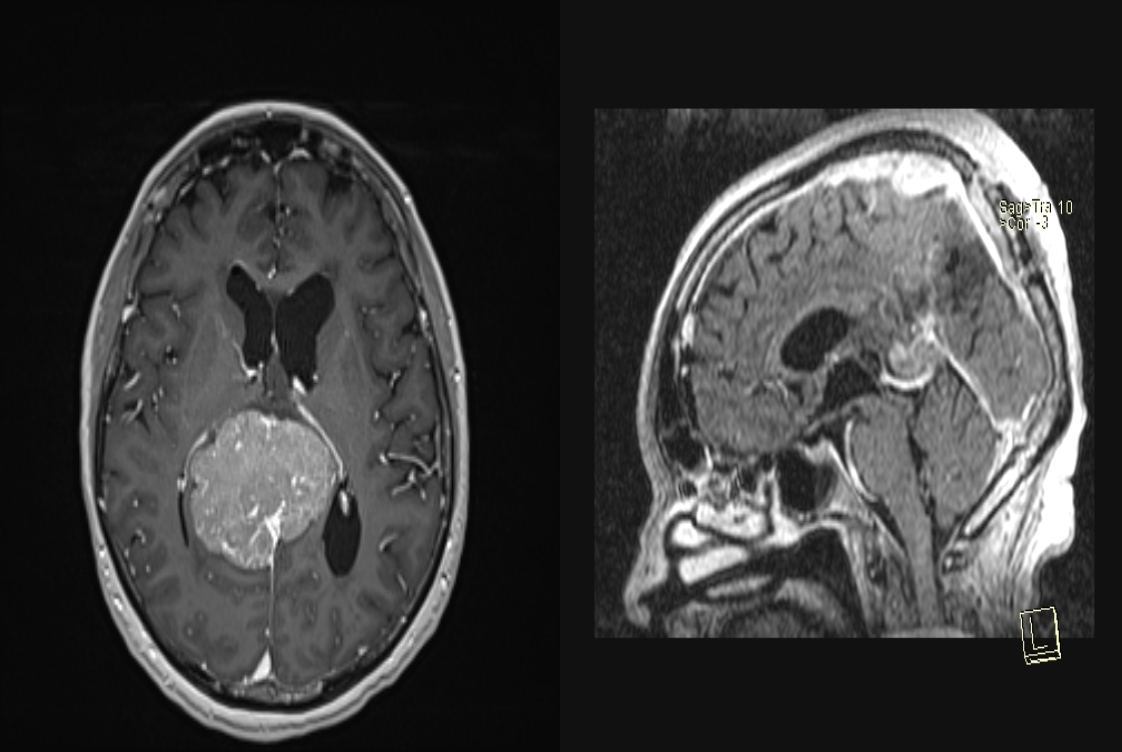

Meningiom

falcotentorial

Prezentare Caz

Femeie, în vârstă de 60 de ani

Simptome - cefalee și ușoară confuzie

Diagnostic - Meningiom falcotentorial

Intervenție - Abord interemisferic minim invaziv keyhole

Status actual - Fără recidivă la 8 ani de la rezecție și 6 ani de la iradiere